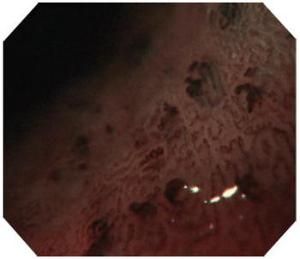

內鏡下表現為各種形態的充血性紅斑(尤其是蛇皮征、馬賽克征、櫻桃紅斑)和糜爛,伴有或不伴有出血。Papazian等描述門脈高壓胃黏膜的胃鏡圖像為一種主要位於胃近端由淡黃色格線鑲嵌的多發性小紅斑,類似馬賽克,並認為這是門脈高壓性胃病的特徵性變化。根據紅斑的數目密集程度可以進行內鏡下分級來評價病變程度。

2.內鏡下可見發生於胃底、胃體部位的黏膜瀰漫充血性紅斑,類似馬賽克,可伴有出血。